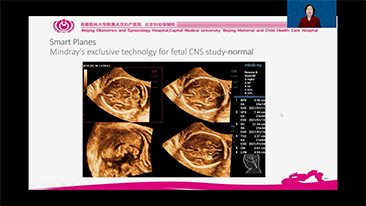

System Nuewa zosta? stworzony specjalnie na potrzeby zdrowia kobiet w okresie przed ci???, w trakcie ci??y i po?ogu. Oparty na zaawansowanej platformie ZST+ oferuje pe?n? gam? inteligentnych rozwi?zań i pozwala na wszechstronn? oraz efektywn? diagnostyk?, wspieraj?c codzienne wyzwania kliniczne.

Technologia